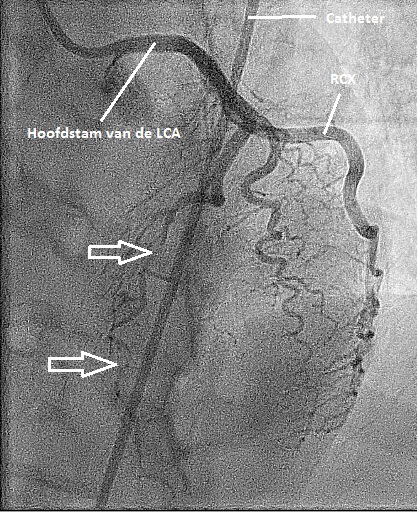

Figuur 2: angiografie beeld van de linkerkransslagader in links laterale 90 graden opname. De witte pijlen geven aan waar het bloedvat (de LAD) is gedisseceerd. LAD = left anterior descending. RCX = ramus circumflexus. LAD en RCX zijn de belangrijke epicardiale vaten. De LAD loopt over de voorwand van het hart en de RCX over de zij-achter wand.